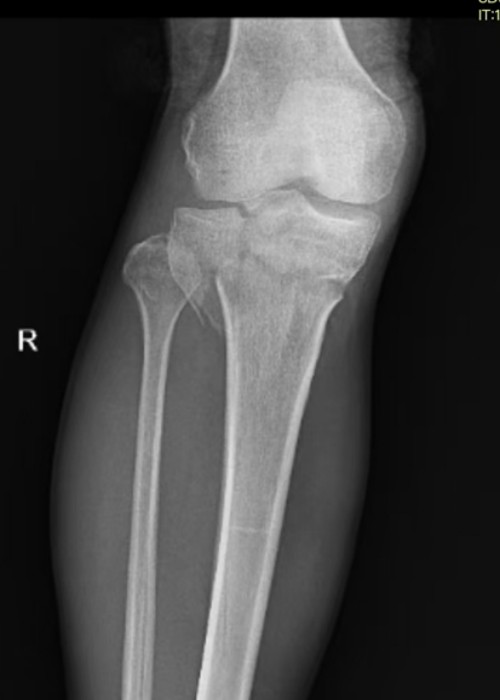

患者尚某因车祸致胫骨上段及胫骨平台骨折入院。此类骨折致残率极高,常规治疗多选择手术以降低致残风险,但尚某基础病情复杂,且家属明确拒绝手术。经骨科主任国华组织科室讨论,决定采用闭合手法复位结合石膏外固定方案,随后,国华与李泰锋医师为其实施精准手法复位,复查显示骨折端对位对线良好。目前患者恢复良好,家属对治疗效果表示高度认可。

复位前